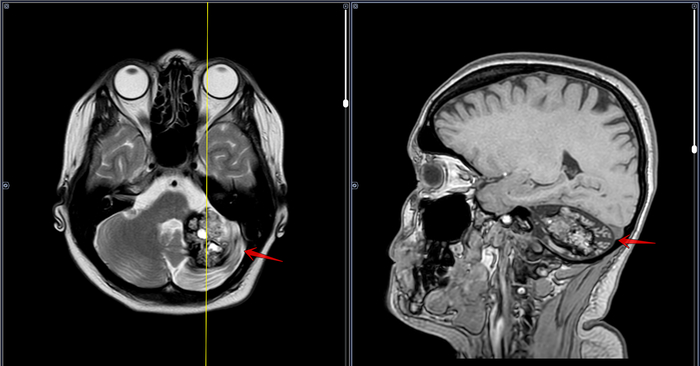

МРТ-Крупная кавернома мозжечка

Серия МРТ

МРТ головного мозга пациента с жалобами на сильную головную боль в затылке, нарушение координации.

В левой гемисфере мозжечка определяется участок патологического МР-сигнала неправильной формы, неоднородно гиперинтенсивный по Т2, Т1, FLAIR со снижением сигнала по периферии (на фоне отложения гемосидерина), гипоинтенсивный по DWI, SWI-восприимчивый, с нечеткими неровными контурами, размерами 3,2х4,1х3,6 см, с признаками перифокального отека. МР картина каверномы левой гемисферы мозжечка больших размеров, малых размеров правой лобной доли

Рек-но: конс. нейрохирурга, решение вопроса об оперативном лечении.

Категория годности по ст.23 а-Д(не годен к в/сл).